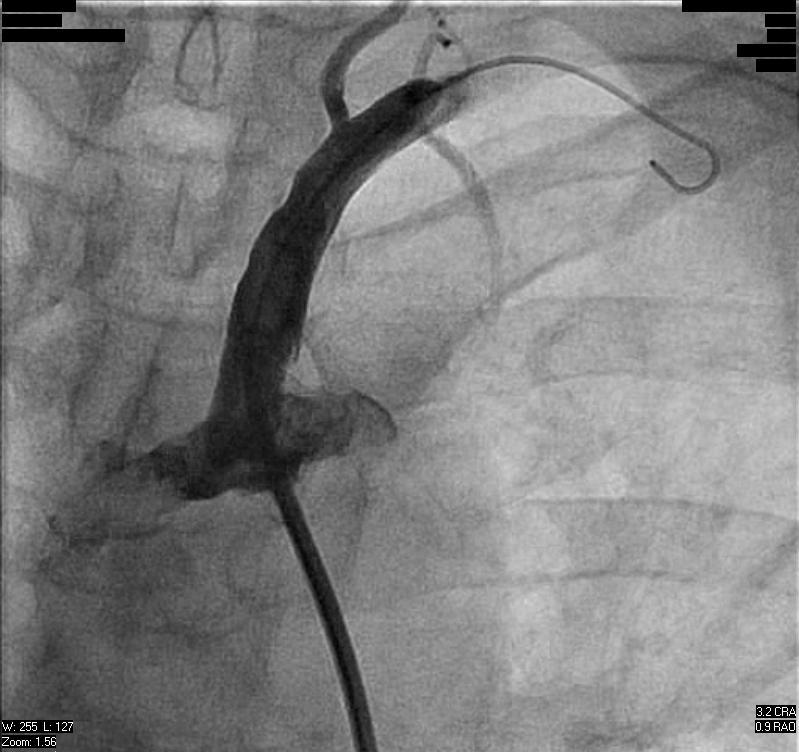

A 57-year-old diabetic woman with a history of three-vessel coronary bypass grafting presented with unstable angina in the form of chest pain occurring at rest. Stress PET-CT showed a dense reversible anterior wall defect and she was referred for urgent cardiac catheterization. Cardiac catheterization was performed via a left radial artery approach. Angiography revealed a patent LIMA-LAD, saphenous vein grafts to the right coronary artery and saphenous vein graft to the ramus intermedius. An 80{8ceaa46882e4d49283ff23b35262537230ad541262f55a031ead545e66522058} stenosis of the left subclavian artery was noted (Figure 1) and was associated with a 25 mmHg pressure gradient:

Given the patient’s profound symptoms and the finding of anterior ischemia on non-invasive testing, it was decided to treat the subclavian lesion. Clinical manifestations and indications for treatment of subclavian stenosis have been reviewed previously.